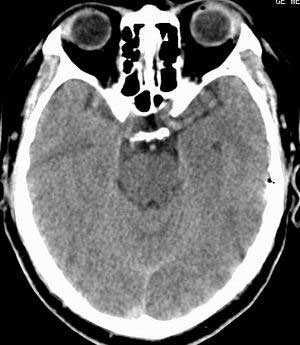

患者男,58岁。耳爆震伤后耳聋2年余,而后双耳道肿胀,间断性流脓。近一月来头痛、恶心、呕吐,右眼红痛,不能入眠。

在平扫时,见右侧枕骨下方小脑半球表面带状模糊稍高密度影,考虑为耳源性脑内感染。

平扫右侧岩骨与枕骨交角内侧脑质内见淡片状密度增高影,内缘清晰。增强图象上未见明显显示。

考虑:1)伪影可能,建议复查头ct平扫。

2)加照头ct骨窗,以显示乳突气房内是否有病变。

右枕颅骨内板下高密度应该是窦的变异,和其症状应该无关,根据病史另找原因吧。[em16]